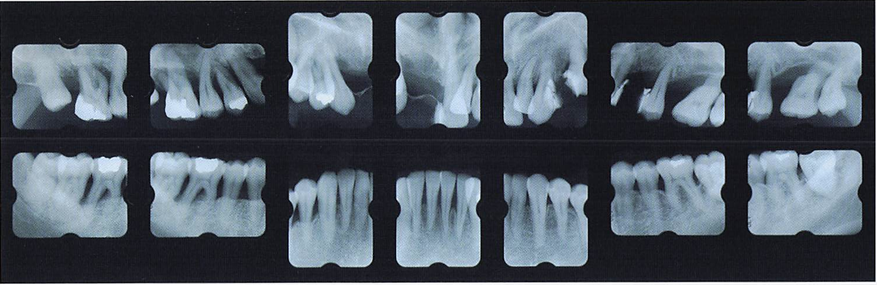

午前-43

32歳の男性。歯ぐきからの出血と排膿が続くようになったことを主訴として来院した。数年前から歯の動揺が気になっていたという。22歳から毎日10本の喫煙をしているが、 全身的な疾患はない。歯周基本治療時の口腔内写真と初診時のエックス親画像を別に示す。 この疾患の特徴はどれか。2つ選べ。

a.栄養障害が原因である。

b.家族内集積が認められる。

c.歯槽骨の破壊が急速である。

d.辺縁歯肉の壊死と潰瘍を認める。

b.c